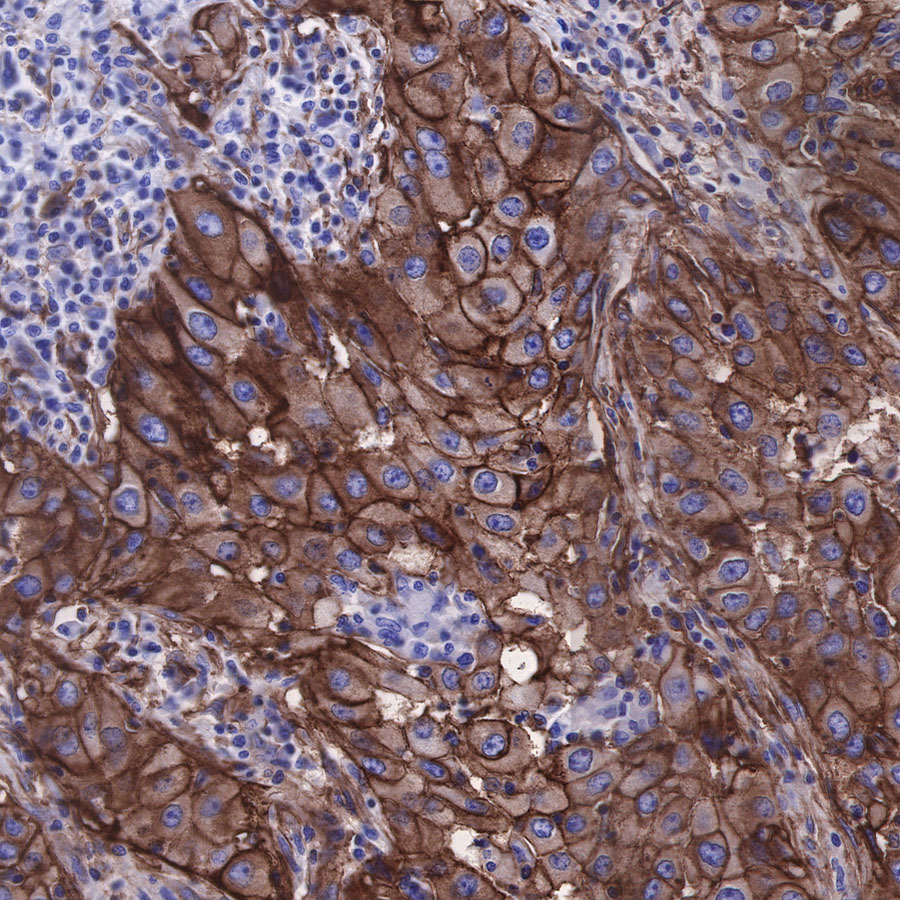

| IHC-P |

1:500 |

|